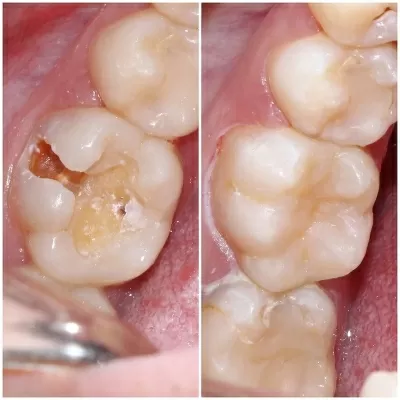

Хочу поблагодарить коллектив стоматологической клиники маэстро!!!Доктора Бардакова Игоря Викторовича и его замечательную команду, за высокий профессионализм чуткость и понимание к своим клиентам!!! Спасибо большое мои дорогие!!! Рекомендую всем кому не безразлична своя улыбка!! Приходите смело в клинику МАЭСТРО не ошибётесь!!!С Уважением Шахова раиса павловна

В стоматологическую клинику МАЭСТРО я пришла по рекомендации.Встретили меня очень тепло.ДОКТОР Игорь Викторович профессионал и умница. Зубы мои стали красивые, а я счастливая.Коллектив у Игоря Викторовича достойный.Как семья.Так приятно.СПАСИБО всему коллективу! Здоровья вам счастья,удачи,мира! Рекомендую всем, кому не все равно как выглядит ваша улыбка и здоровье ваших зубов читать далее